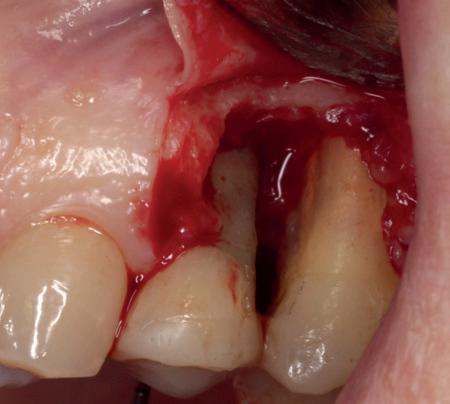

Casus

In deze casus is extractie van de 37 geïndiceerd in verband met een fistel en restpockets, zoals zichtbaar op de röntgenfoto’s (afbeelding 1). Duidelijk te zien is de forse peri-apicale ontsteking en het botverlies bij de 37, dat zowel richting buccaal als linguaal doorloopt. De 37 wordt atraumatisch verwijderd. Er is aan de linguale zijde veel bot verloren en er is sprake van een perforatie aan de buccale zijde.

Er wordt besloten om botmateriaal te plaatsen in de extractie-alveole. Vervolgens wordt het afgesloten met een titanium versterkt d-PTFE membraan (afbeelding 2). Na vier weken wordt het membraan verwijderd.

Zes maanden na extractie wordt het implantaat 37 geplaatst. Er is sprake van een goede genezing en de processushoogte en -breedte zijn behouden en opgebouwd. Ook is er zichtbaar gekeratiniseerd weefsel

1 2 Ridge preservation met d-PTFE membranen 35

gewonnen. De wond kan na het plaatsen van een healing abutment primair gesloten worden (Afbeelding 3a-3d).